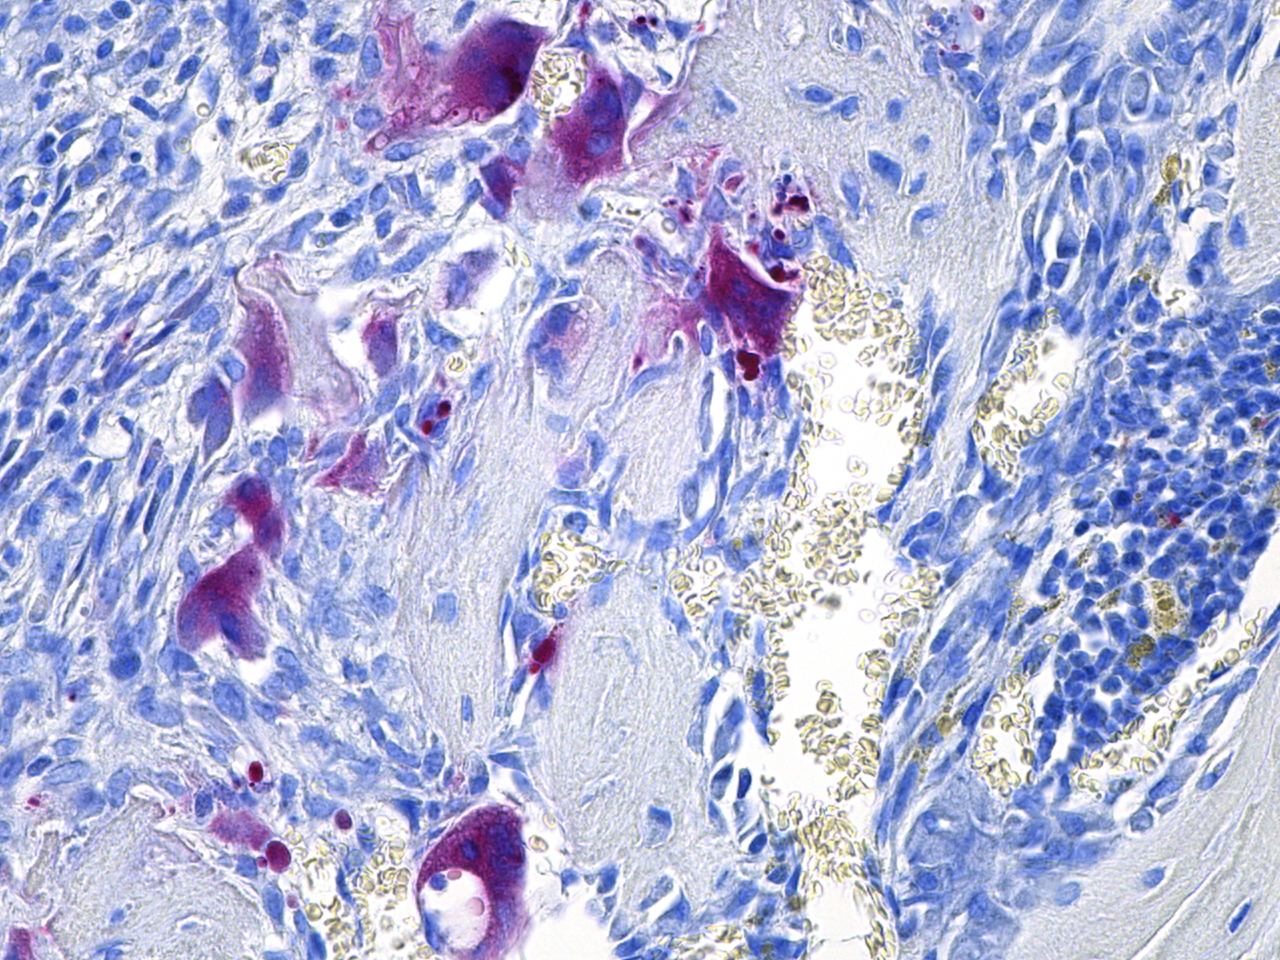

The MD Anderson Bone Histomorphometry Core Laboratory provides histomorphometric analyses of non-decalcified bone specimens. Bone specimens are processed for histology and can be stained for static and dynamic histomorphometric analyses (Osteomeasure or the Bioquant Osteo II system). The core can provides slides, data, training

Research Histology Core Lab: Bone Processing, Embedding and Sectioning

Bone Histomorphometry Core: Staining and Analysis